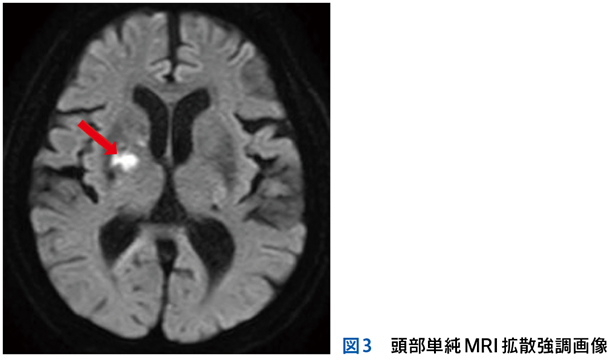

Case 1

独居の高齢者が自宅内で倒れている状態で発見され搬送された。最終健常は5日前。頻脈,SpO2低下,意識障害,感染徴候を伴う褥瘡,急性腎障害,高ナトリウム血症,クレアチンキナーゼ高値,炎症反応亢進,膿尿がみられている。

▶ この患者は何らかのイベントを契機に動けなくなり,長時間倒れていたものと推測される。多数ある「プロブレム」の中には,最初のイベントに直接起因するものもあるかもしれないが,大部分は倒れていた結果として生じてきたもの(最初のイベントの診断という観点では「ノイズ」)だろう。こういった患者が「脱水症」とか「横紋筋融解症」としてのみ治療されているケースをよく見かけるが,これは表層に現れた二次的,三次的な現象を取り上げているだけであり,最初のイベントの鑑別と治療が本来必要である。